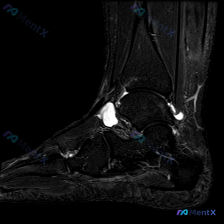

今天看到一个很有讨论价值的读片病例,整理一下信息和分析思路给大家参考。 病例基本信息 问题:患者主诉踝关节感觉有软组织积液,请读片判断 影像:踝关节MRI-脂肪抑制序列-轴位单张图像 影像详细评估 这是踝关节远端水平的轴位扫描,先给大家整理一下观察结果: 1. 骨骼:胫骨远端、腓骨远端骨髓信号正常,...

看到一份只有踝关节MRI影像的病例,这里给大家整理一下读片思路和容易踩的坑,一起来讨论下。 病例核心信息: 这是踝关节MRI-T2序列轴位图像,主要的异常发现如下: 1. 解剖结构基本正常:跟腱、腓骨长短肌腱、内踝后方各肌腱走行连续,信号都正常;距骨、跟骨骨髓信号没有异常水肿或破坏,没有骨折或明显韧...

拿到这张踝关节MRI T2轴位片,问题问软组织液有什么表现,整理一下病例信息和分析思路给大家参考: 基本影像信息 这是踝关节MRI T2序列轴位图像,核心发现是: 1. 骨骼:距骨等主要骨性结构轮廓连续,无明显骨皮质中断,骨髓无大范围明显T2高信号水肿 2. 肌腱韧带:外侧腓骨长短肌腱走行区可见不规...